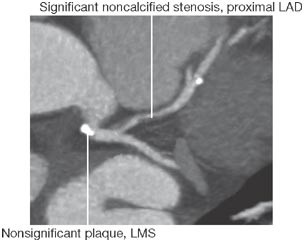

Background A 75-year-old male with a history of myocardial infarction and recent transient ischemic attack was referred to a cardiology clinic for preoperative evaluation before a cystectomy. Transthoracic and transesophageal echocardiography revealed a mobile mass on the right coronary cusp of the aortic valve. Multislice CT demonstrated a significant narrowing in the proximal left anterior descending coronary artery.

Investigations Physical examination, chest radiography, laboratory testing, electrocardiography, transthoracic and transesophageal echocardiography, multislice-CT coronary angiography, pathological and histological examination of the surgically excised tissue.

Diagnosis Papillary fibroelastoma of the aortic valve in conjunction with coronary artery disease.

Management Surgical excision of the mobile lesion and an end-to-side anastomosis of the left internal mammary artery to the left anterior descending coronary artery.